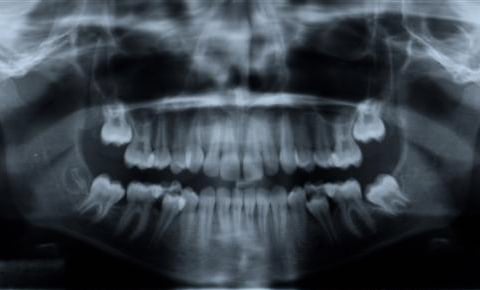

Digital Panoramic X-Rays

Panoramic x-rays offer patients a complete detailed image of the entire mouth including the teeth, jaw (upper and lower), sinuses, and TMJ.

It provides a complete picture on how everything looks and relates to each other.

Panoramic X-Rays

Panoramic x-rays offer patients a complete detailed image of the entire mouth including the teeth, upper and lower jaws, sinuses and TMJ.